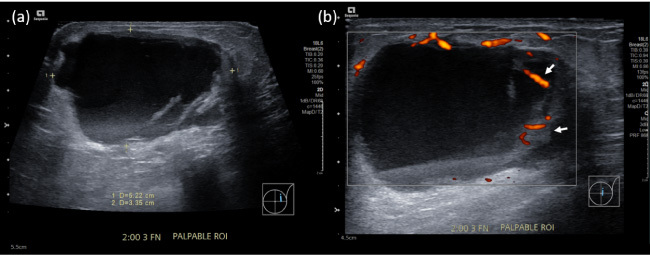

An 85-year-old Chinese lady presented with a 5-day history of a painless left breast lump. There was no fever, nipple discharge, or history of trauma. She had a past medical history of atrial fibrillation that was managed with an oral anticoagulant. Mammography demonstrated a dense mass in the upper outer quadrant of the left breast. Ultrasound showed an irregular, heterogeneous 4.7 cm lesion containing debris and cystic spaces with raised peripheral vascularity at the 2 o'clock position, 3 cm from nipple. No internal vascularity was detected. This was managed as a haematoma and rivaroxaban was withheld. Follow-up imaging 3-weeks later showed persistence of the lesion. Bedside needle aspiration yielded haemoserous fluid with immediate reduction in size of the lesion. However, 2 weeks after aspiration, there was recurrence of the 'haematoma'. Multidisciplinary review of the clinical history, examination and imaging was sought, and biopsy of the irregularly thickened areas with vascularity along the periphery of the lesion was recommended. Vacuum-assisted biopsy was performed, and histology returned as metaplastic carcinoma. A recurring 'haematoma' should always prompt a search for a secondary cause, with features such as irregular thickened walls and papillary/nodular components requiring further evaluation with biopsy for histopathological correlation.